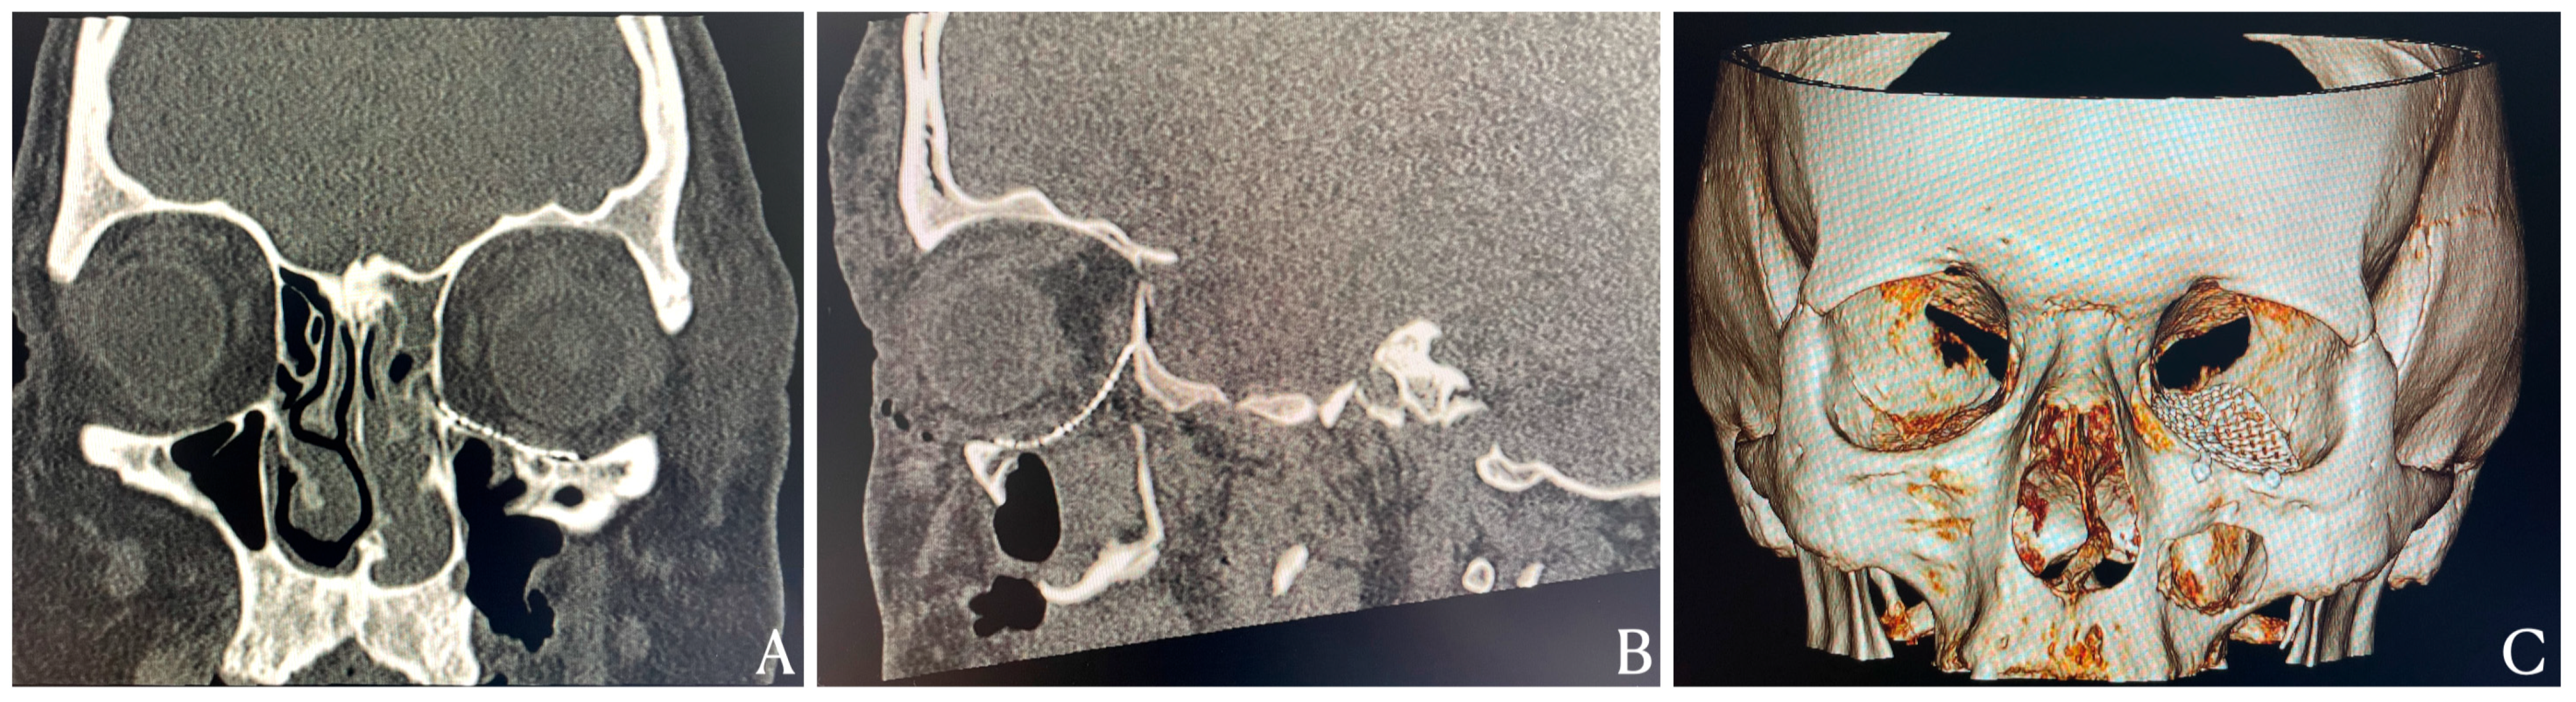

An Exceptional Case of Blow-Out Fracture with Complete Globe Dislocation into the Maxillary Sinus: Diagnostic Imaging and Surgical Reconstruction